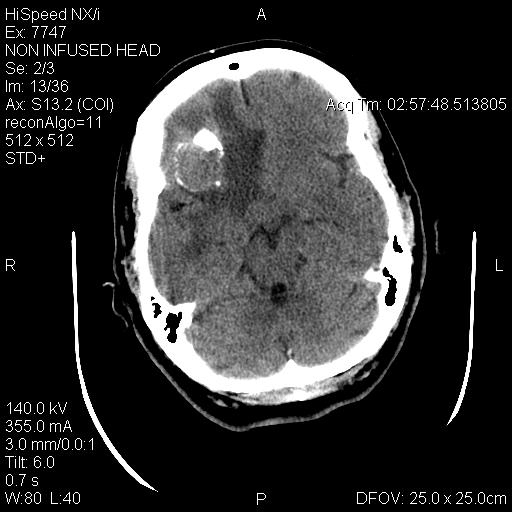

Radiology of the case:

T1-weighed MR images demonstrate an extraaxial, dural based mass involving the right supraorbital region  (Panel A and B). The mass shows homogeneous enhancement  (Panel C). CT scan demonstrates as well as rim calcification (Panel E). On T2-weighed imagers, significant vasogenic edema is demonstrated despite the small size of the lesion and the extraaxial location (Panel D).